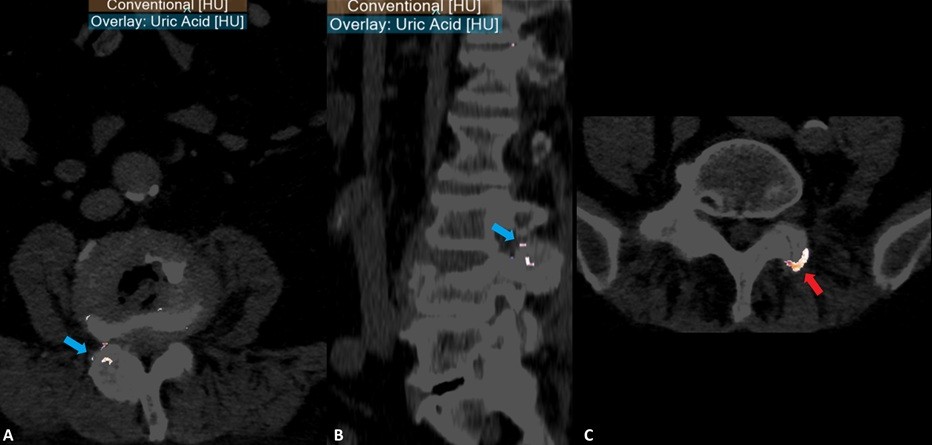

A tomografia computorizada espectral demonstrou uma lesão com densidade em vidro despolido, calcificada à periferia, a envolver as facetas articulares direitas de L3-L4 (figura 3). A lesão condiciona ligeira erosão das facetas articulares (setas vermelhas em figura 3). O estudo espectral com realização de reformatações dirigidas à identificação de cristais de urato revelou a presença de cristais em topografia periarticular interfacetária na região da lesão referida acima (A e B na figura 4). Considerou-se tratar-se, assim, de um tofo gotoso interfacetário da coluna lombar.

Figura 3: Imagens de tomografia computorizada espectral da coluna lombar (Phillips 7500TM, (A) janela tecidos moles axial, (B) janela óssea axial, (C) janela óssea sagital) visualizando-se lesão de densidade em vidro despolido (setas azuis), calcificada à periferia, condicionado erosões nas facetas articulares de L3-L4 direitas (setas vermelhas).

Figura 4: Imagens de tomografia computorizada espectral da coluna lombar (Phillips 7500TM , mapa de sobreposição de imagem convencional com deposição de ácido úrico, (A) axial, (B) sagital, (C) axial) revela deposição de cristais de monourato de sódio na localização da lesão localizada entre as facetas articulares L3-L4 direitas (setas azuis em A e B), rodeados por infiltrado inflamatório. Adicionalmente, verificou-se a presença de cristais de monourato de sódio noutras localizações da coluna lombar (seta vermelha).